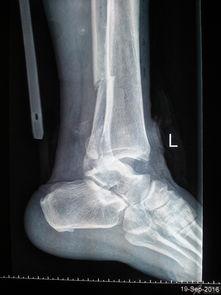

三、脚踝脱臼的图片

为了让你更直观地了解脚踝脱臼,以下是一些真实的图片:

从这些图片中,你可以看到脚踝脱臼后的严重程度,以及肿胀、畸形等症状。